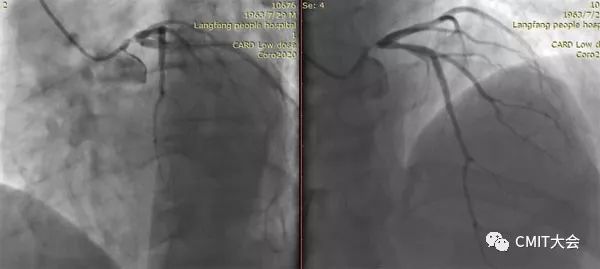

➢ CASE 1

➢ CASE 2

右冠起源异常,开口于左冠窦

➢ CASE 3

AL1.0

➢ CASE 4

➢ CASE 5

升主动脉造影未见桥血管显影,原位血管造影也没发现竞争血流迹象,可以确定桥血管已闭塞,必要时可以借助冠脉CTA辅助诊断